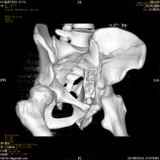

Уважаемые коллеги! Хотелось бы услышать совет по тактике лечения представлленого больного.Поступил после лечения в одном изотделений области. Травма 2,5 месяца назад. После выведенияиз шока был произведен остеосинтез перелома бедра, предплечья, до перевода к нам проводилосьвытяжение по оси шейки бедра за стержень, введенный в большой вертел. На сегодня деформацияригидна, клинически мобильности не определяется. Заранее признателен. P.S. Данный вид травм не включен в перечень "высокотехнологичных операций", направить длялечения по квотам Минздрава очень сложно.

Это обзорные и косые снимки

Привет, Леонид. Оскольчатый высокий двухколонный перелом в такие сроки трогать не надо, т.к. это про такие переломы сказано: "кто с ножом на Ж. пойдет тот в ней и останется...".

Может быть неплохой результат при консервативном лечении и ранних движениях.

Если заболит после начала нагрузки в 4-6 месяцев - эндопротез.